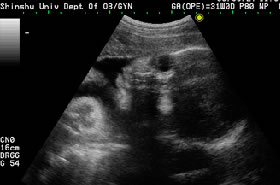

超音波検査では、妊娠5週には胎児の入っている袋(胎嚢)が子宮の中にあることを確認できます。多胎妊娠かどうかの診断も早い週数から行うことが必要であり、全妊娠期間を通じて、とても有用 な検査です。

〔写真右:妊娠7週の胎嚢と胎児〕